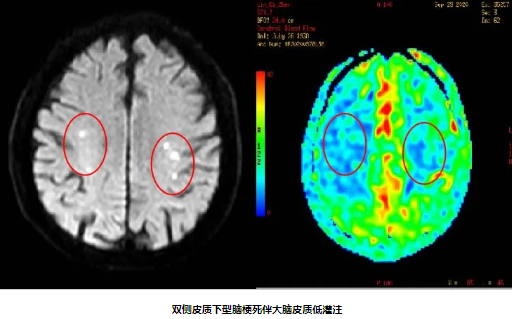

82岁男性,因“双下肢无力10天”入院,既往有“高血压病”史10年。入院后完善颈动脉彩超及影像学检查提示:1.分水岭梗死(双侧皮质下型)2.双侧颈内动脉重度狭窄 3.窦性心动过缓。经颈动脉狭窄MDT团队充分讨论,精心安排,在心血管内科中心的协助下,脑血管病专科团队克服了患者高龄、心动过缓等危险因素,成功给予患者双侧颈动脉支架同期植入,患者症状得到明显好转。